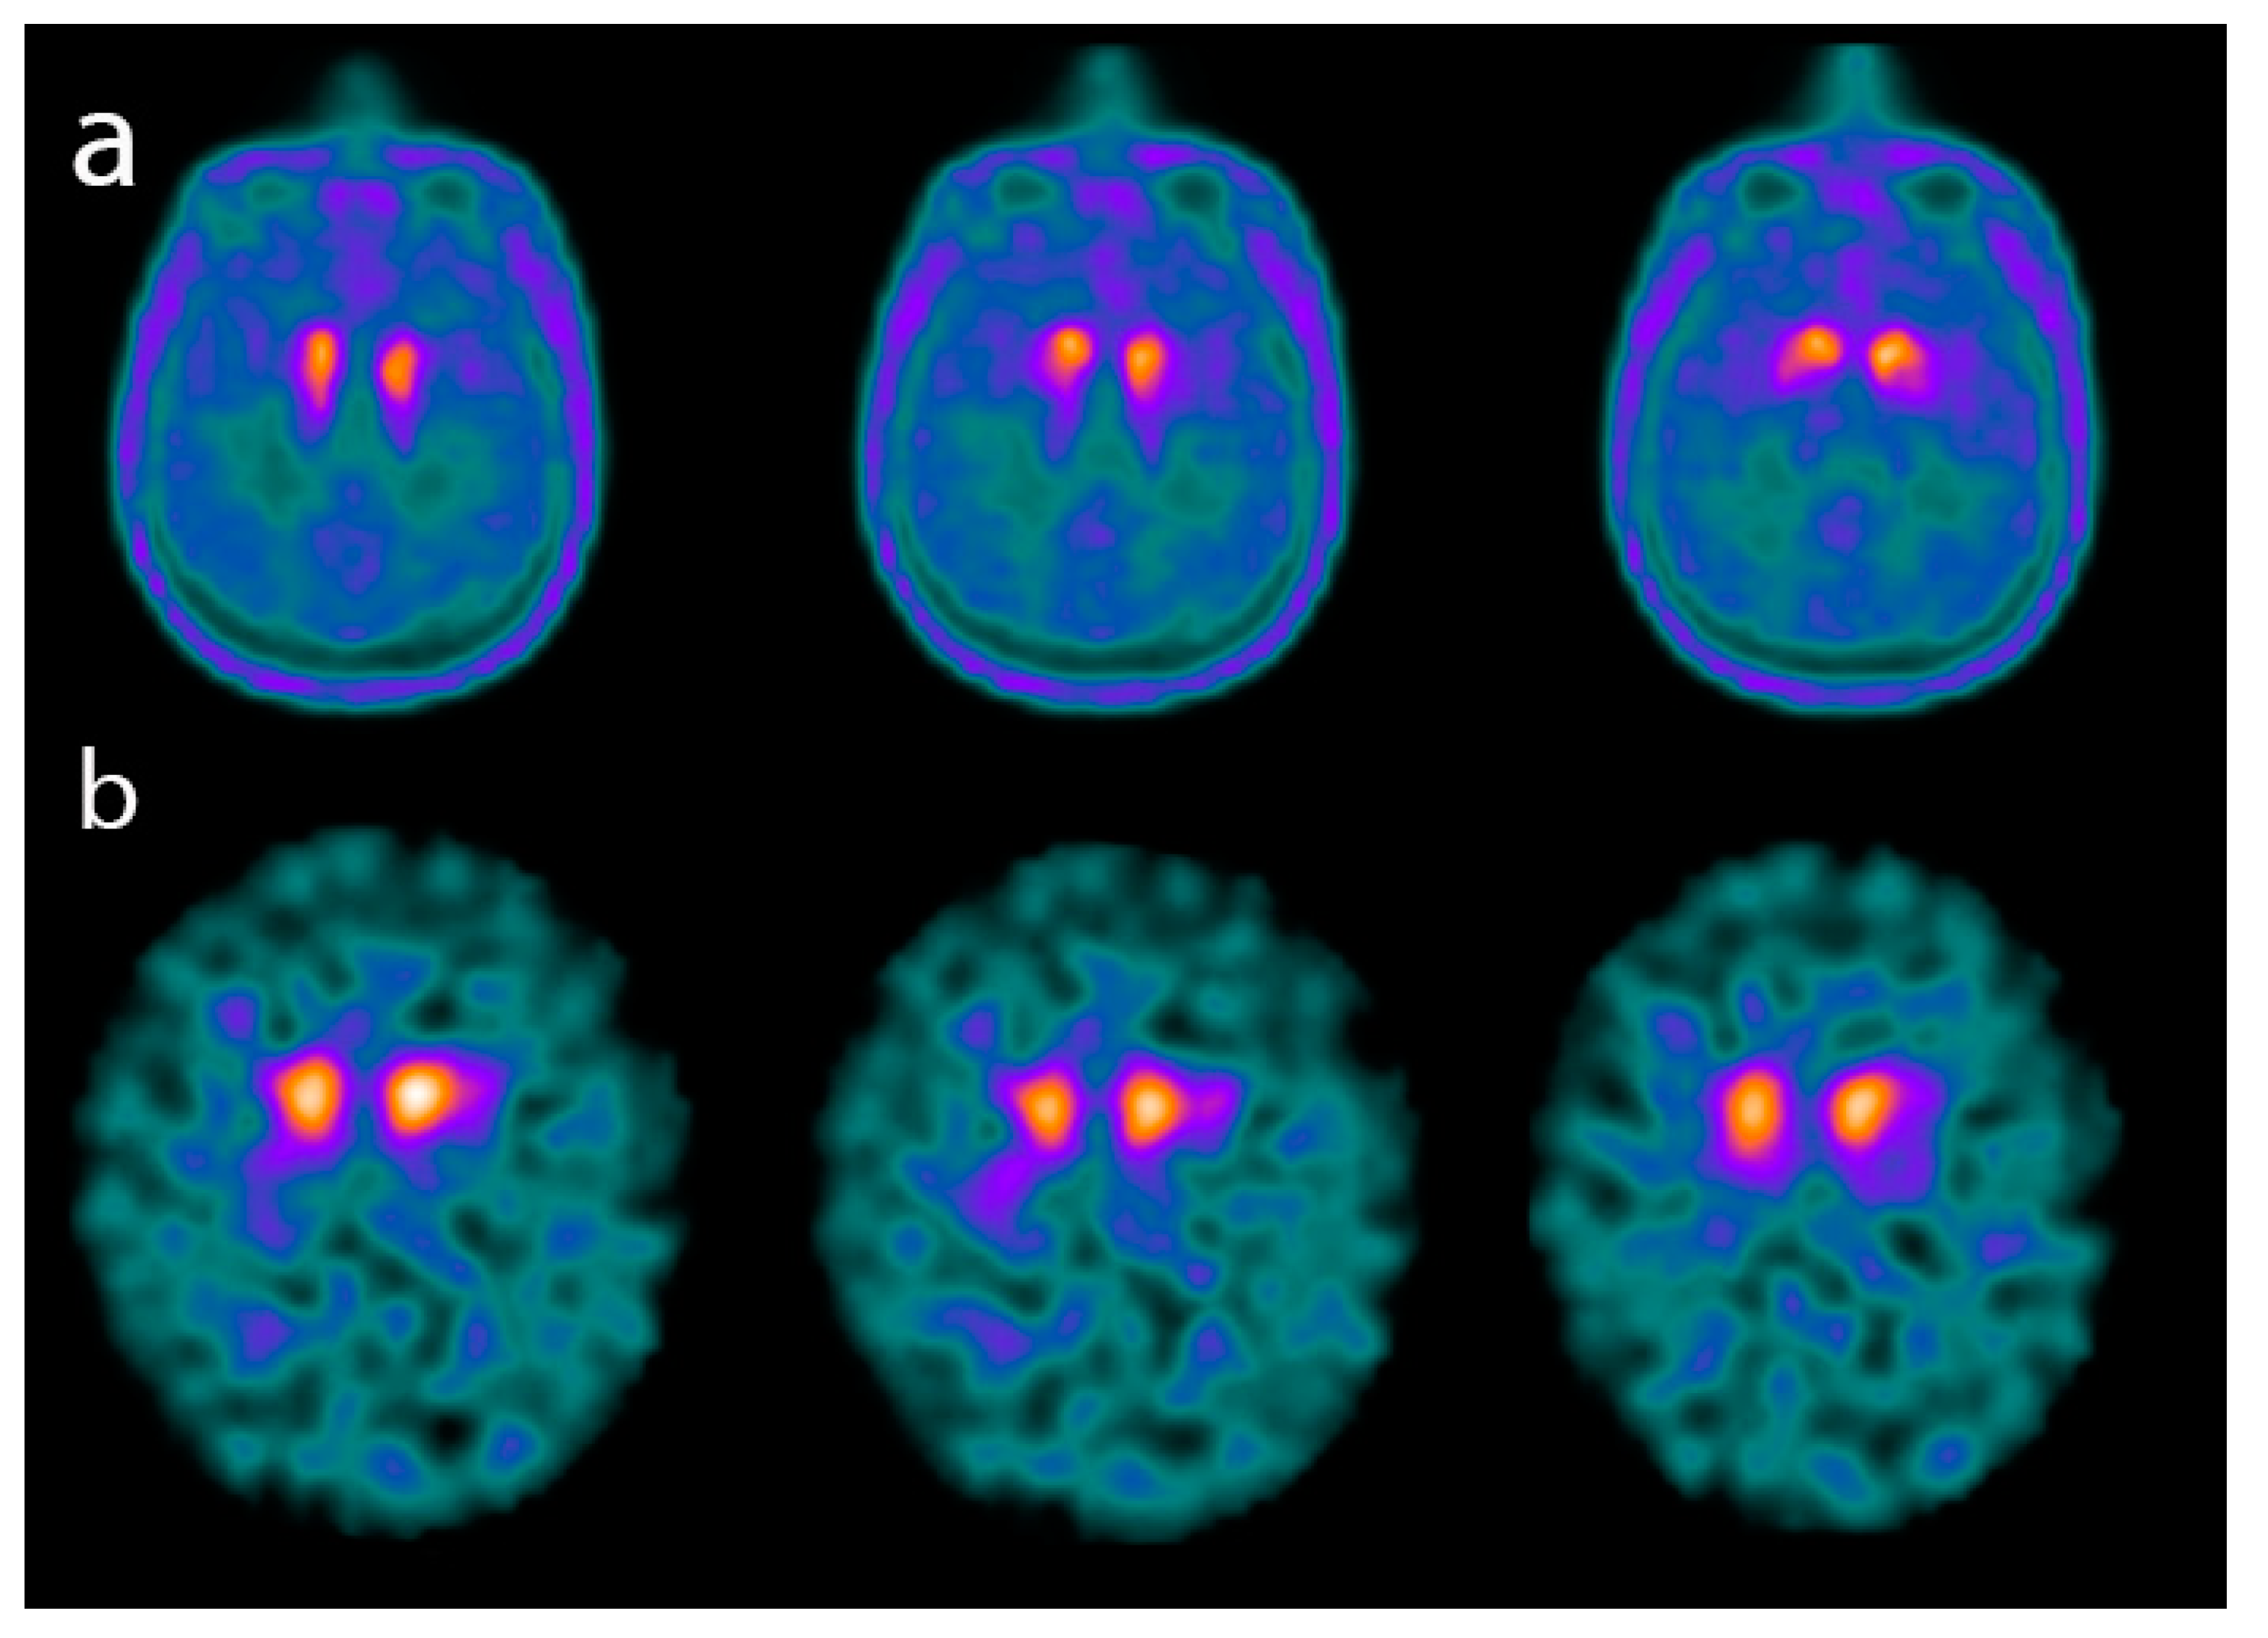

4.1. Dopamine Transporter (DAT) Imaging in SNCApathies

- McCleery, J.; Morgan, S.; Bradley, K.M.; Noel-Storr, A.H.; Ansorge, O.; Hyde, C. Dopamine transporter imaging for the diagnosis of dementia with Lewy bodies. Cochrane Database Syst. Rev. 2015, 1, CD010633. [Google Scholar] [CrossRef] [PubMed]

- McKeith, I.; O’Brien, J.; Walker, Z.; Tatsch, K.; Booij, J.; Darcourt, J.; Padovani, A.; Giubbini, R.; Bonuccelli, U.; Volterrani, D.; et al. Sensitivity and specificity of dopamine transporter imaging with 123I-FP-CIT SPECT in dementia with Lewy bodies: A phase III, multicentre study. Lancet Neurol. 2007, 6, 305–313. [Google Scholar] [CrossRef]